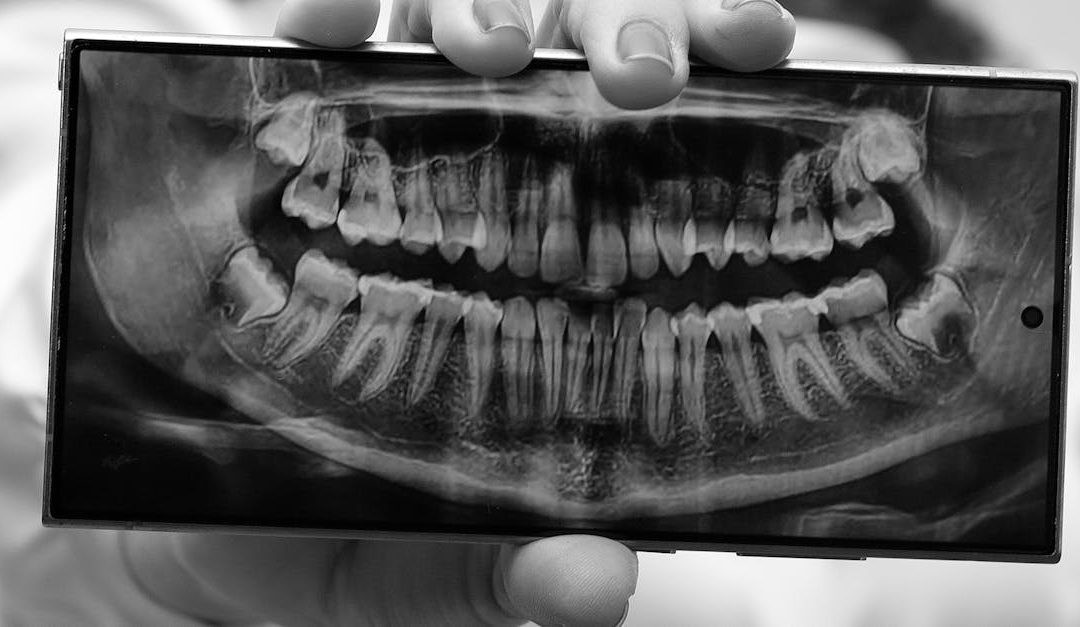

Le panoramique dentaire offre une vue d'ensemble de toute la dentition sur une seule image. On y voit les dents, les mâchoires, les sinus, les articulations temporo-mandibulaires et les dents de sagesse. C'est souvent le point de départ d'un premier bilan complet, notamment chez un nouveau patient ou lors d'un suivi orthodontique.

Beaucoup de patients regardent la radio s'afficher sur l'écran sans vraiment savoir ce que leur dentiste y cherche. Une carie ? Un problème d'os ? Une dent de sagesse qui pousse mal ? En réalité, une seule image peut contenir plusieurs informations à la fois, et certaines d'entre elles changent complètement le plan de traitement.

Une radio peut révéler une carie qui se développe entre deux dents, un abcès en formation à l'apex d'une racine, une perte osseuse liée à une maladie parodontale ou une dent incluse qui n'a pas encore fait son éruption. Ces situations n'ont souvent aucun symptôme pendant des mois. Agir avant que la douleur s'installe, c'est généralement agir avant que les dégâts s'aggravent.